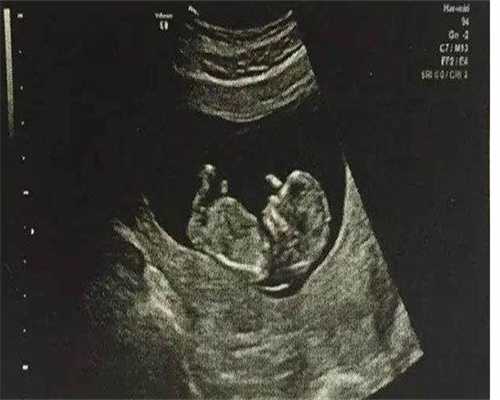

第四代试管婴儿技术可从事自然试管受精培养和体外受精术前培养两种技术,备孕成功率更高。第四代试管婴儿技术可以更好地优化体外受精的环境,受精卵可以得到更充足的营养供给,多种抗生素可以杜绝病菌对受精卵的污染,从而提高受精率。

此外,与传统的 试管婴儿 相比,四代 试管婴儿 技术能为受精卵提供更充足的营养物质和更好的液体培养环境,有利于受精卵的发育和成熟,从而进一步提高受精率。常见的试管技术,根据专家的选择,还可以提高孕妇的妊娠并发症概率。

总的来说,四代试管婴儿技术比传统的试管婴儿技术成功率更高,受精率也更高,但要想彻底掌握其效果,还需要一定的时间,只有根据专业的诊断和精心的护理,才能更完美地移植受精卵,从而起到提高个人成功率的有效权威。

四联试管婴儿成功率是技术上令人惊叹的试管婴儿成功率,指的是经过试管婴儿过程后,无论是成功怀孕还是手术后产生健康的概率和可能性。目前,四镜一丝的成功率相当高,约为 60-70%。它为许多想要孩子的不幸夫妇提供了一种新的可能性。